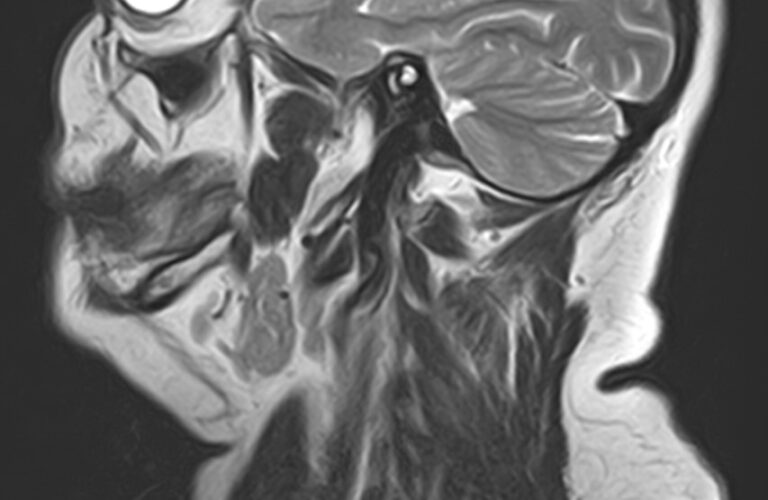

Магнитно-резонансная томография на сегодняшний день является наиболее информативным исследованием слюнных желез. Метод позволяет получить изображения мягкотканных структур с высокой детализацией, при этом отсутствие вредного ионизирующего излучения обеспечивает безопасность процедуры и позволяет проводить ее неоднократно по мере необходимости. Это бывает важно для оценки эффективности проводимого лечения.

В нашей клинике МРТ слюнных желез выполняется на высокопольном томографе экспертного класса TOSHIBA VANTAGE TITAN 1,5 Тесла. Аппарат производит сканирование в трех различных плоскостях в виде тончайших послойных срезов с шагом от 1 мм. Высокая индукция магнитного поля, используемая в аппарате, обеспечивает превосходное качество изображений. Кроме того, с помощью инновационных компьютерных приложений реконструируются объемные изображения исследуемой зоны, что улучшает визуализацию и повышает точность и достоверность диагностики.